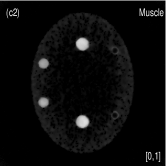

Fig. 4 shows the decomposed material images by the Direct Inversion, the PWLS-EP-LOOP and the PWLS-TNV- method. The left corners of the to the column of Fig. 4 show enlarged rods that are highlighted with white dashed boxes in decomposed material images. Table 2 summarizes the means and noise STDs of ROIs of decomposed basis material images. The volume fraction (VF) accuracies were , , and for the Direction Inversion, the PWLS-EP-LOOP and the PWLS-TNV- method, respectively. Compared with the Direct Inversion and the PWLS-EP-LOOP method, the proposed PWLS-TNV- method increases the VF accuracy by and respectively.

Table 3 summarizes the average electron densities of contrast rods and RMSE() of electron density for the three MMD methods. The RMSE() was , and for the Direct Inversion method, the PWLS-EP-LOOP method and the proposed PWLS-TNV- method, respectively. The proposed PWLS-TNV- method suppressed noise, decreases crosstalk and increased decomposition accuracy in the material images, while maintaining high image quality.